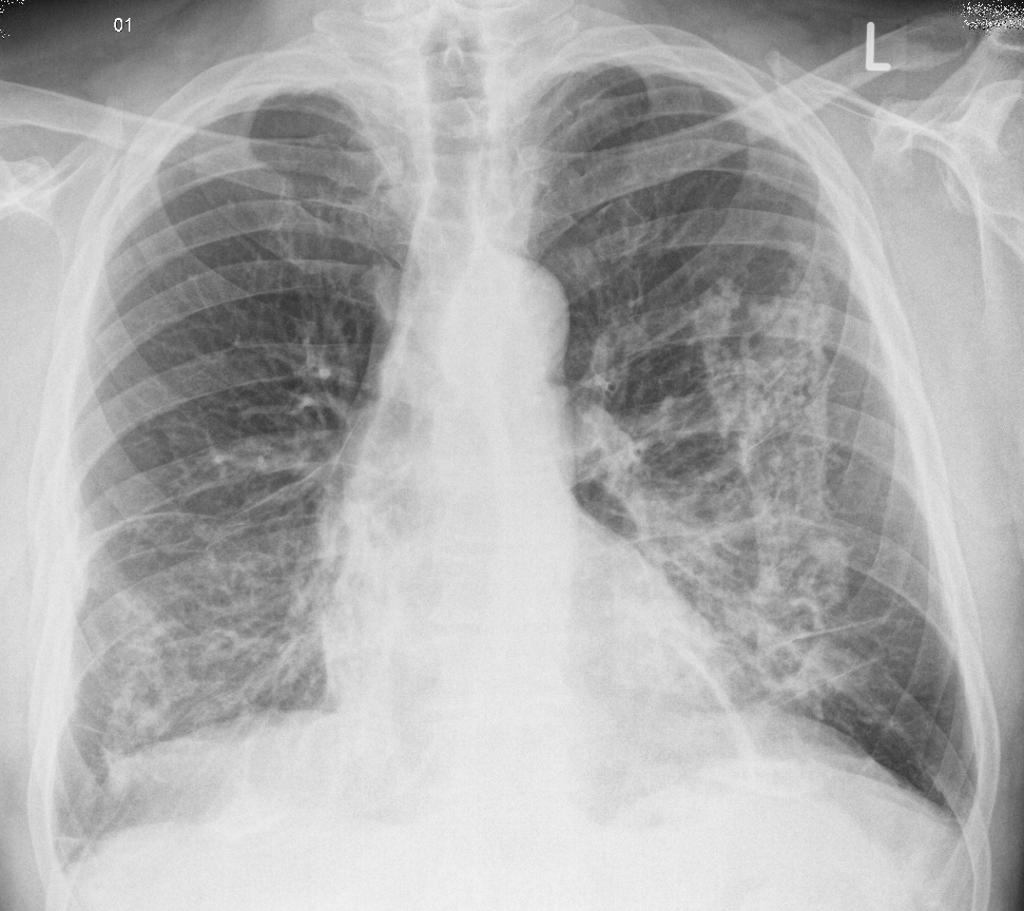

- Mạn tính: Xuất hiện sau khoảng 10-30 năm tiếp xúc với bụi silic ở nồng độ thấp. Bệnh thường không có triệu chứng rõ ràng, nhưng có thể phát hiện qua chụp X-quang phổi. Triệu chứng điển hình là sưng phổi và hạch bạch huyết ở ngực gây khó thở. Bệnh nhân có thể không nhận ra mình bị bệnh cho đến khi bệnh tiến triển nghiêm trọng.

- Chụp X-quang phổi hoặc CT phổi để quan sát tổn thương